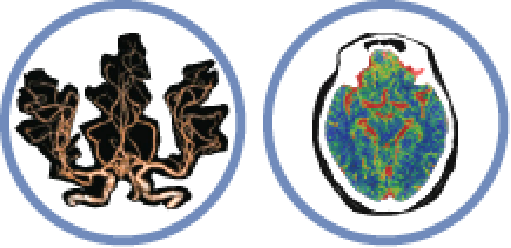

Precision in Neurology

▪ Cerebral Hemorrhage Analysis

▪ Brain Perfusion Analysis